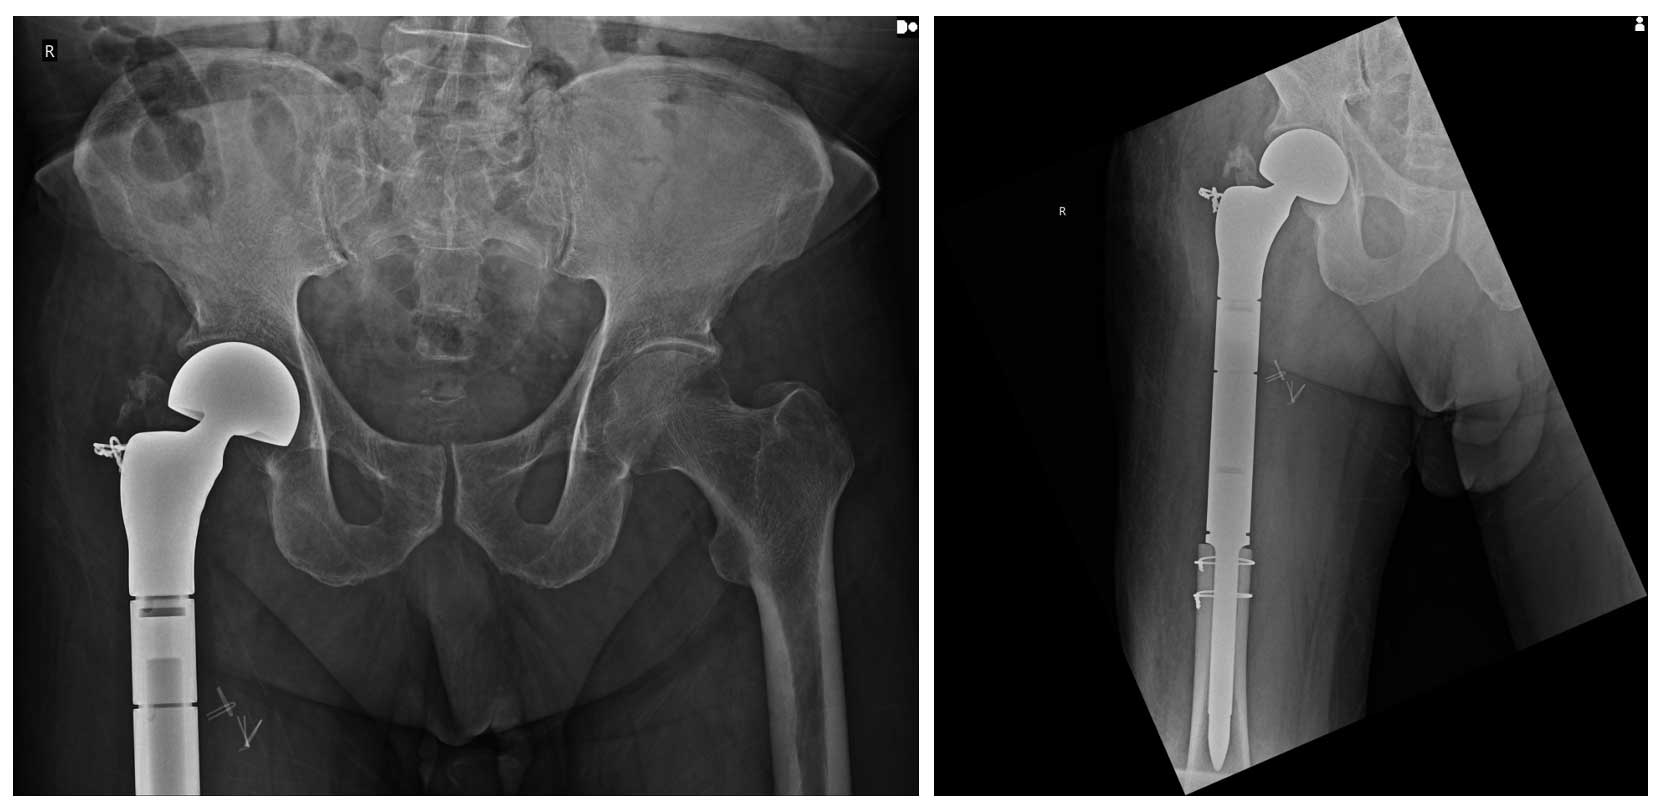

Ameliyat Sonrası: Röntgende proksimal femur rezeksiyonu sonrası tümör protezi ile rekonstrüksiyon görülmekte.